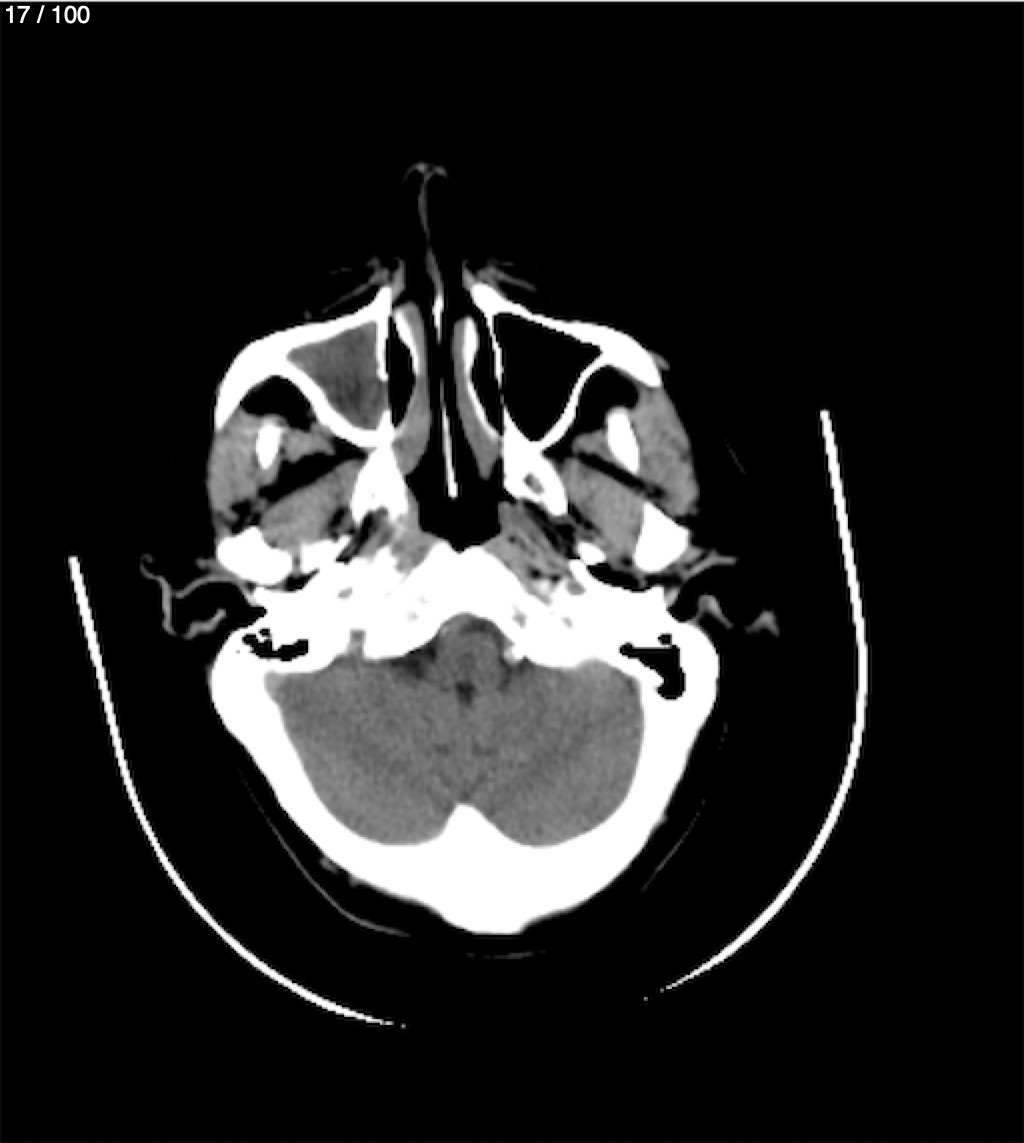

Valentin Perez Gomez 69A - T.C Craneo